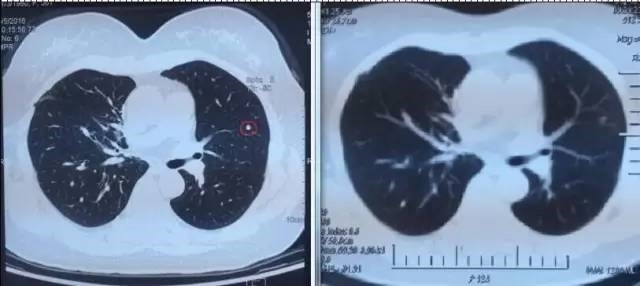

左图红色圈内是A45治疗前三个肺癌病灶,右图为治疗后病灶消失

患者一年多来一直听到的都是坏消息,治疗做完后回家了,也是不放心,直到9月6日复查结果出来,肺上三个病灶消退,一年多来终于等来一个好消息,开心的不要不要的,笑容重新回到了她的脸上,先生说,现在太太每天在家开心的逗孙子玩,自己感觉体力充沛了许多,每天可以走七八千步锻炼。苏州大学附属肿瘤医院专家建议说,患者现在暂时不需要治疗了,三个月后再进行一次A45巩固治疗,增强免疫即可 。